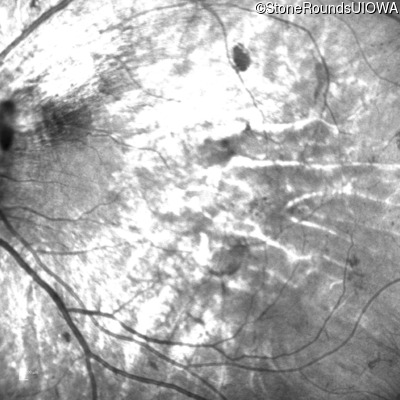

Infrared Fundus Photograph - Left - 5/200

Exemplar